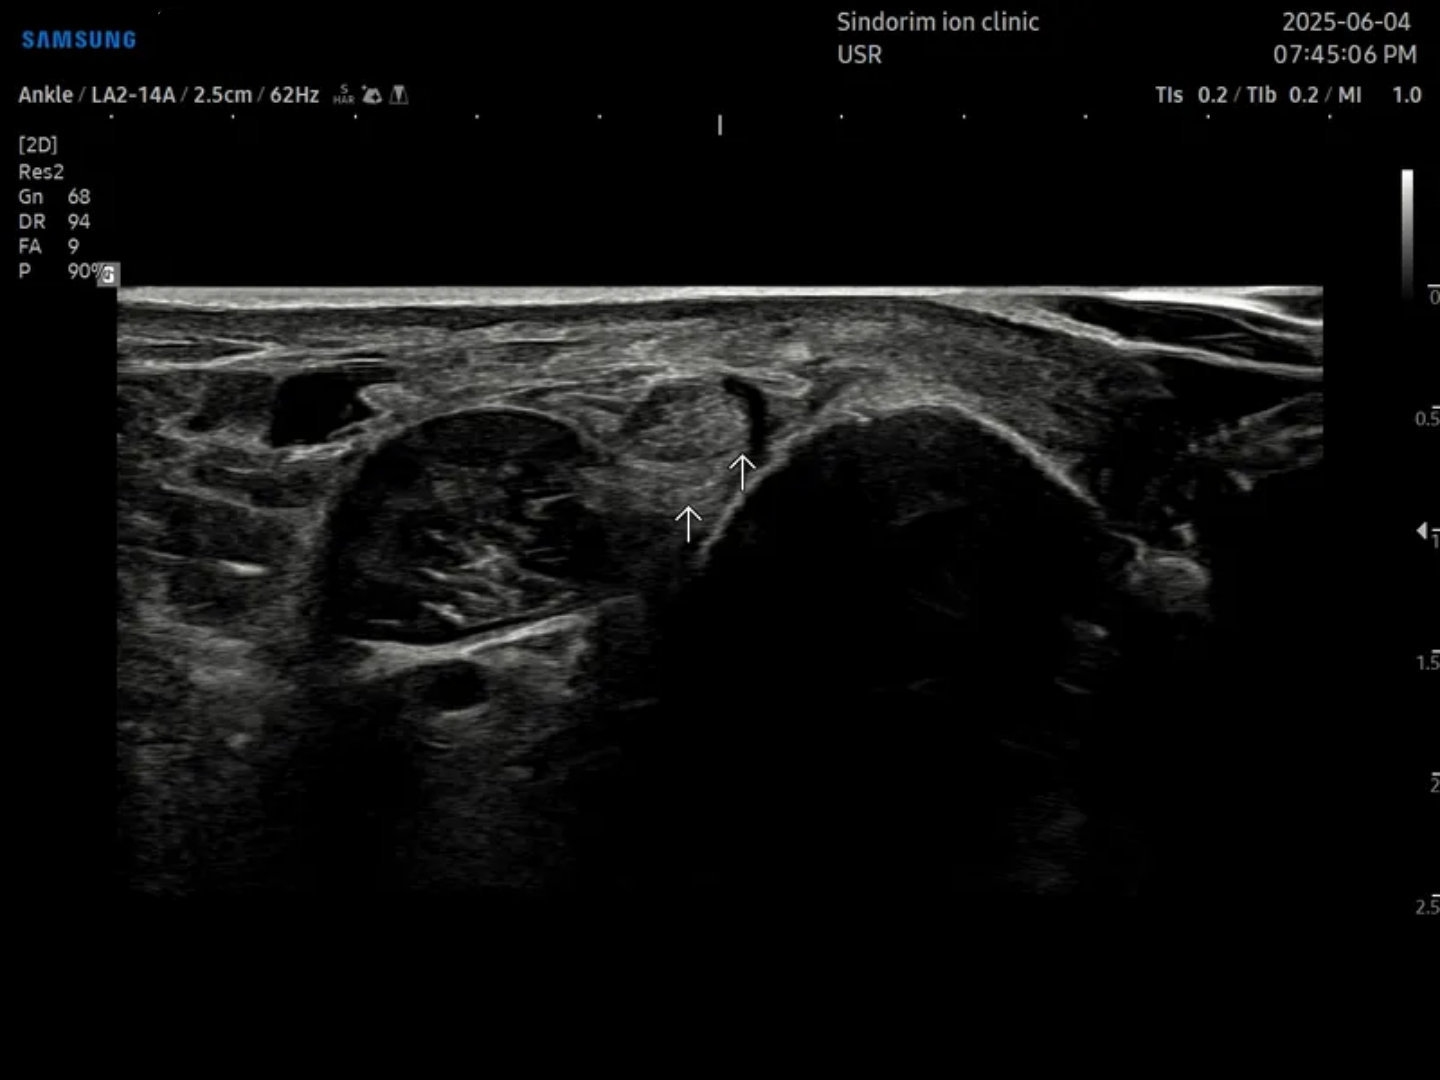

- 치료기간 : 25 . 4 . 19 ~ 25 . 9 . 0

- 치료횟수 : 20 회

치료 전

좌측: 비골근건 우측 ATFL

치료 후 : 비골근 건은 10회차에 마무리 / ATFL은 20회차에 마무리